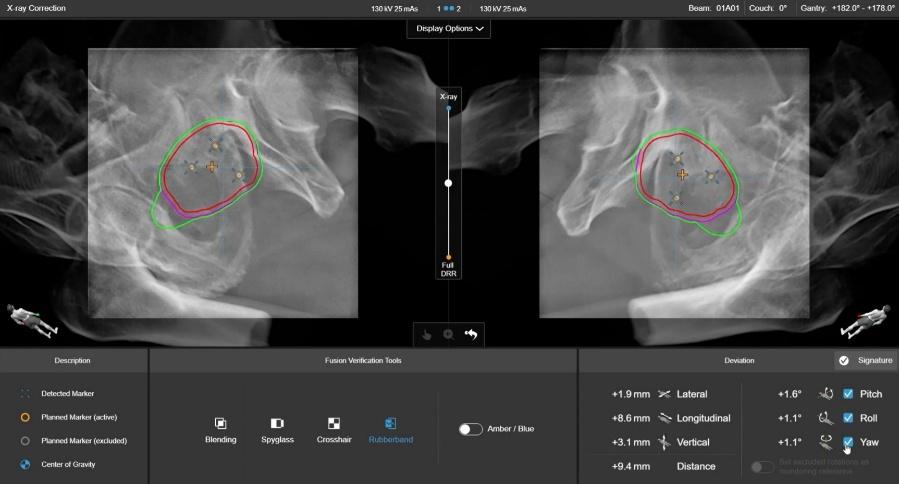

ステレオX線画像誘導システム(ExacTrac Dynamic)

ExacTrac Dynamic は、2台のX線装置により骨構造などの内部解剖情報を撮影し、治療計画画像と高速に照合することで、サブミリメートルレベルの高精度な患者位置合わせを可能にします。特に、高精度な脳定位放射線治療(SRS/SRT)の実施において有効です。

また、光学技術とサーモグラフィを用いた熱監視システムにより、患者さんの体表面を三次元的に認識し、治療中の体動をリアルタイムで監視します。患者さんの位置が設定された許容範囲から外れた場合には、自動的に照射を停止し、再位置合わせを行うことが可能です。

前立腺マーカートラッキング

ExacTrac Dynamic のマーカートラッキングは、前立腺の放射線治療において、前立腺内にあらかじめ留置した小さな金属マーカーを目印として位置を確認する技術です。前立腺は膀胱や直腸の状態によってわずかに動くことがあるため、治療のたびに正確な位置を確認することが重要です。

ExacTrac Dynamic では、治療前に2方向からX線撮影を行い、金属マーカーの位置を治療計画時の位置と比較することで、前立腺のずれを高精度に確認します。その結果に応じて患者さんの位置を細かく調整することで、前立腺により正確に放射線を照射し、周囲の正常組織への影響を可能な限り抑えた治療を目指します。